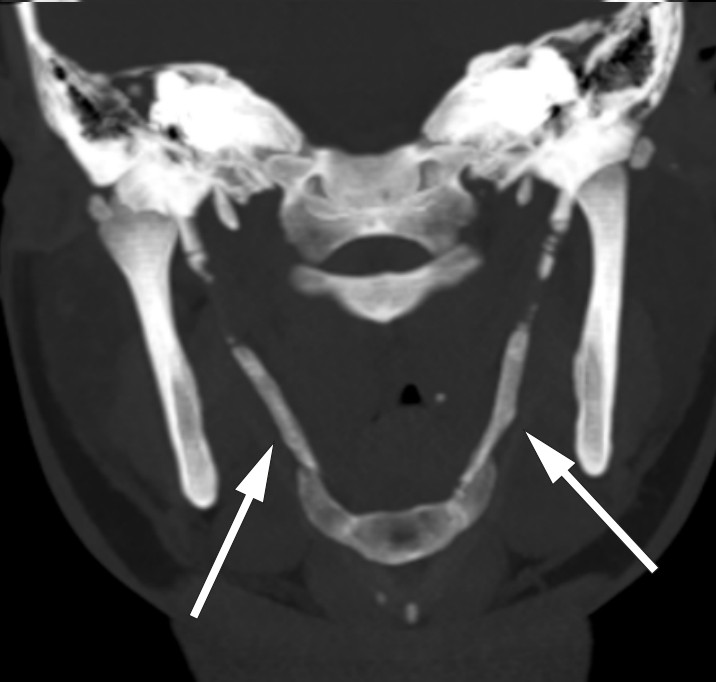

The symptoms were triggered and exacerbated by leaning or rotating the head to the right. The patient reported having experienced a similar, transient episode two years earlier. There was no history of head or neck trauma. Clinical examination was normal, apart from soreness upon palpitation of the peritonsillar region and the left side of the neck. A comprehensive work-up with neurophysiological testing, imaging and an otorhinolaryngological examination revealed normal findings. A CT scan of the neck revealed bilateral calcification of the stylohyoid ligaments (see arrows), which could explain the patient's symptoms.